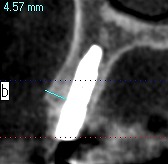

術後のCTになります

頬側の骨幅も維持できていました